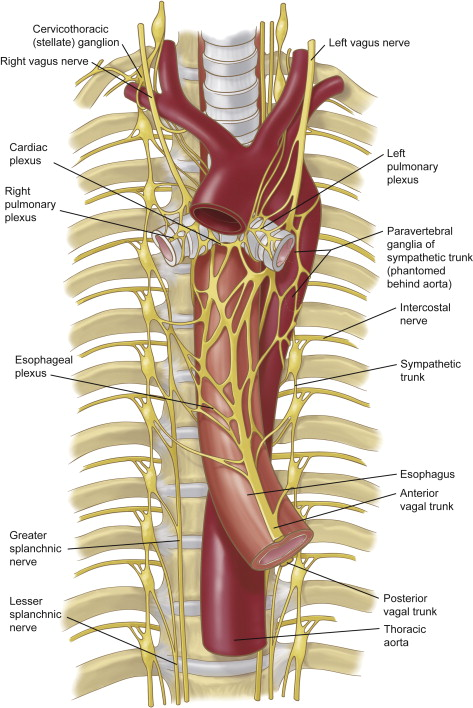

Sympathetic chain

Intercostal nerves

Greater splanchnic nerve

Lesser splanchnic nerve

Aorta